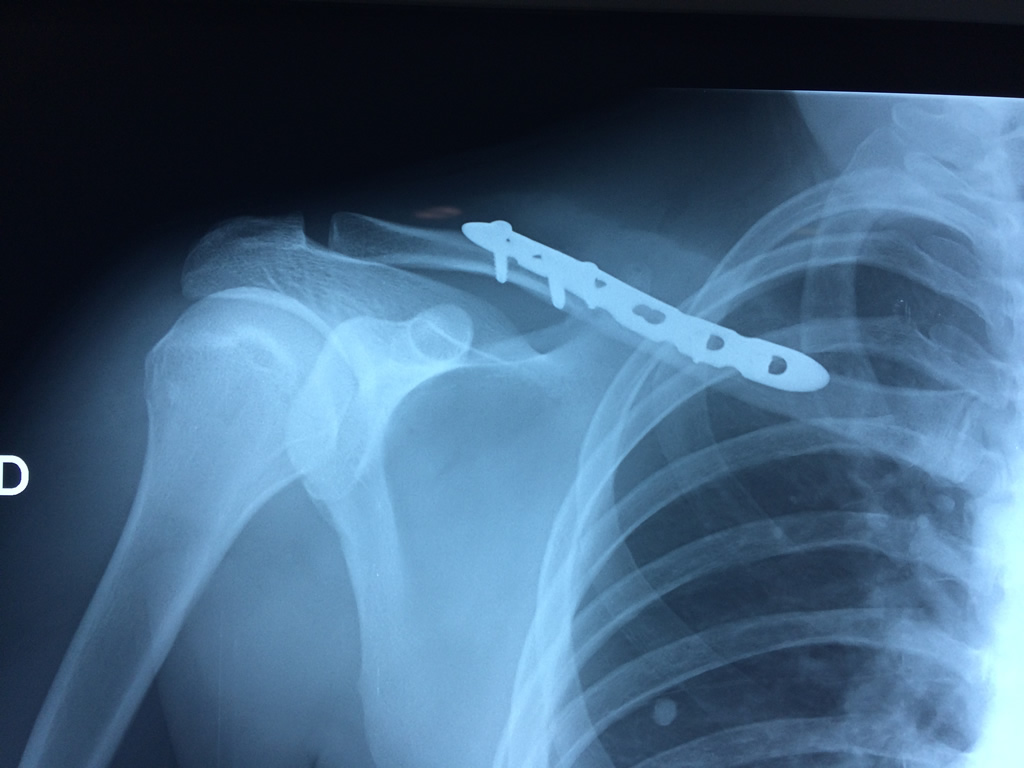

Cirugías de Húmero - Clavícula